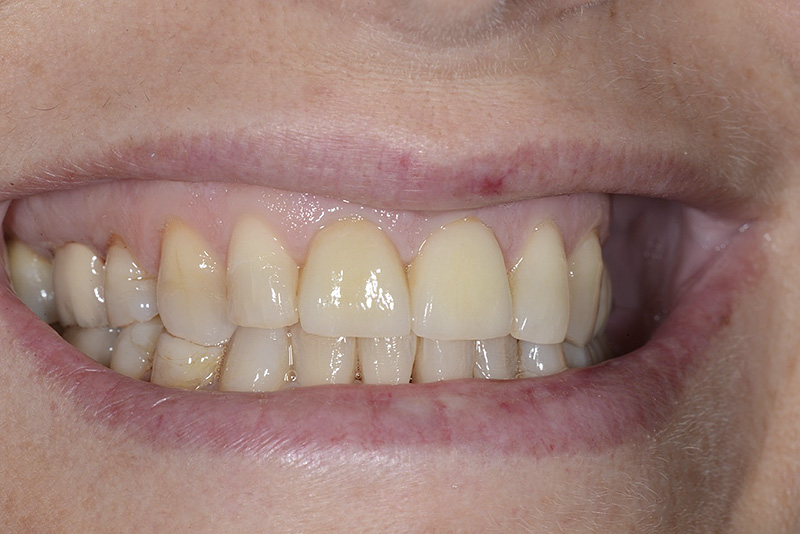

PREMESSA: in seguito all’estrazione dell’incisivo laterale superiore di destra, resasi necessaria per cause batteriche, si decide di affrontare il caso con il posizionamento di un impianto in sostituzione dell’elemento mancante dopo guarigione del sito infetto. Con tecniche rigenerative sia dei tessuti ossei mancanti a causa dell’infezione pregressa, sia dei tessuti gengivali che appaiono inizialmente troppo spostati in alto, si ripristina una corretta morfologia delle parabole (contorni) gengivali e delle papille interdentali (triangoli di gengiva tra due denti vicini).

Vengono utilizzati 2 tipi di provvisori: il primo, cementato ai denti vicini, viene utilizzato dal momento dell’estrazione del dente fino ad impianto osteointegrato (circa 6 mesi); il secondo, avvitato direttamente all’impianto, ha una funzione di prova estetica ma soprattutto di guida per la maturazione dei tessuti gengivali peri-implantari portandoli verso la maturazione completa prima di posizionare la corona finale in disilicato di litio.